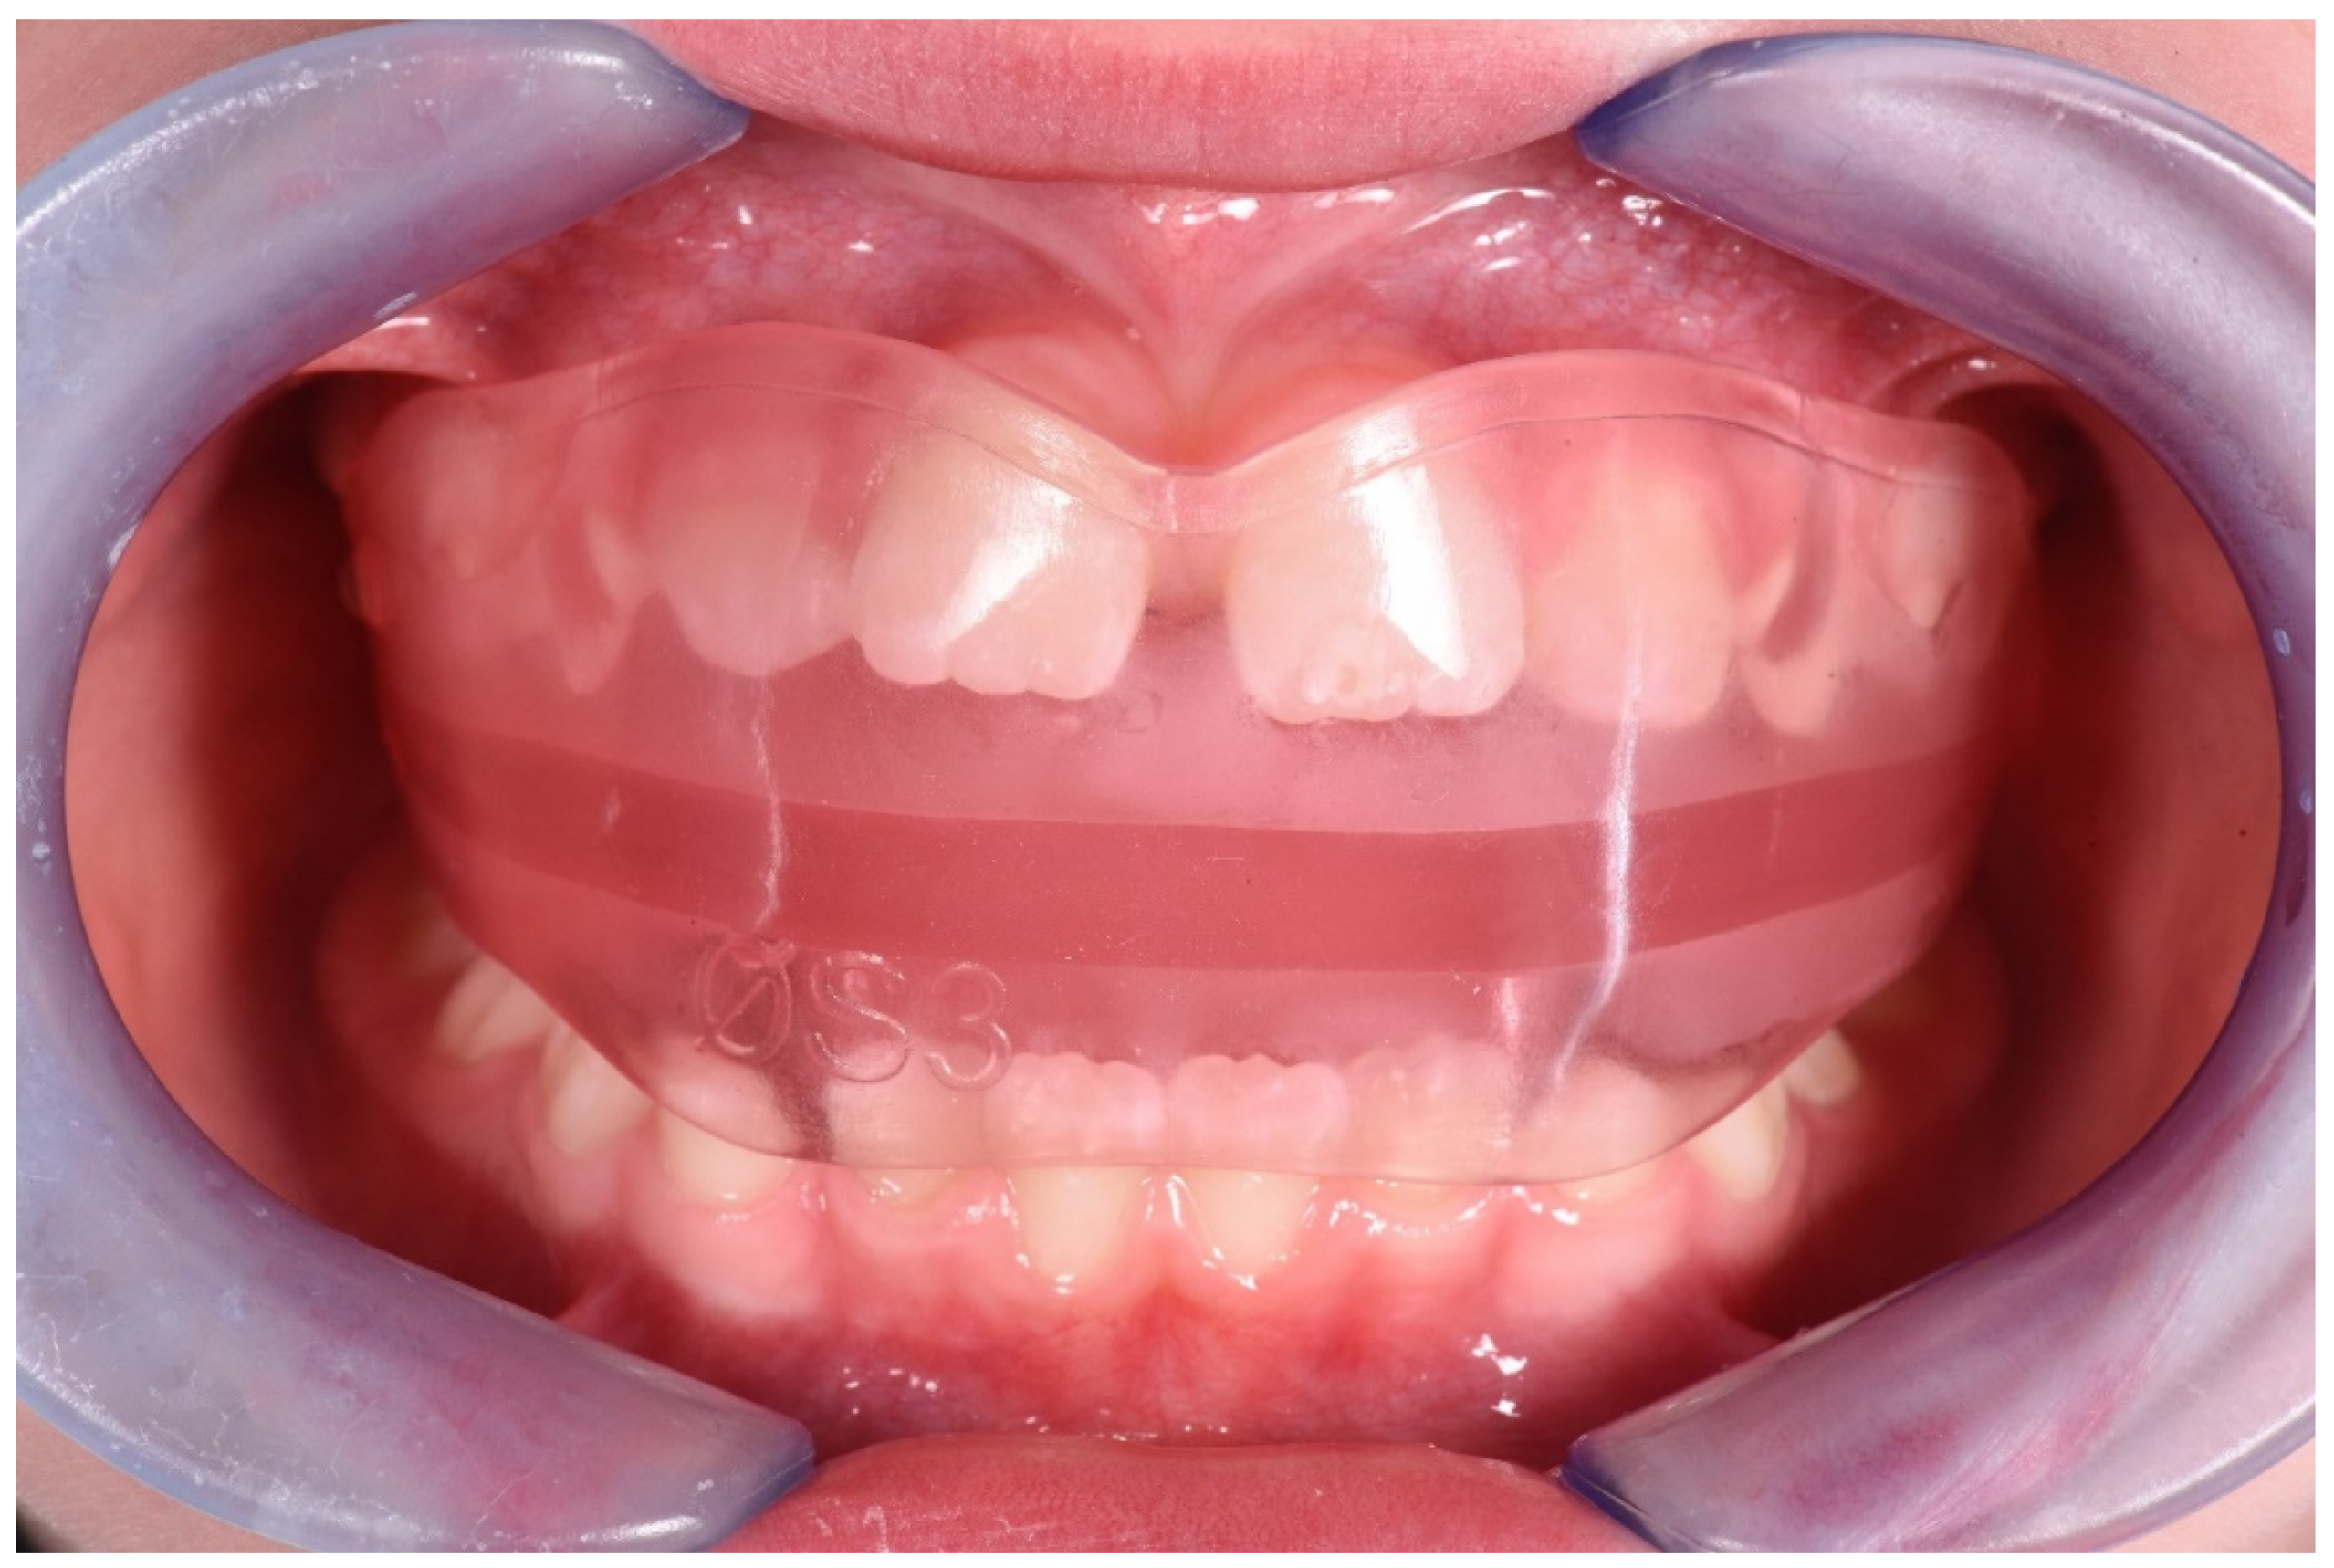

3.1. Clinical Case #1